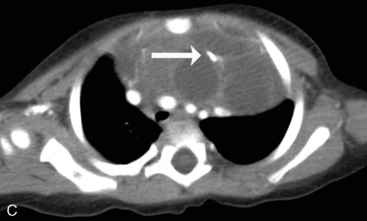

Children older than 6   years have mediastinal structures comparable to those of adults. The thymus shadow, seen in the upper third of the chest at the mediastinum, has bilateral lobes. The thymic silhouette blends almost imperceptibly with the cardiac silhouette, because it occupies contiguous space, giving the appearance of a widened mediastinum. It can produce a triangular shadow, resembling the sail of a boat (called the sail sign). The thymus is most often visualized on the chest radiograph from birth to 2   years of age, but may persist up to 5   years of age6,16,17,25 (Fig. 10-9).

image image

Fig. 10-9 Normal thymus. A, This supine anteroposterior film demonstrates the right lobe of the thymus projecting over the right upper lung field, creating the appearance of a widened mediastinum. The triangular shape (arrows) is the classic appearance of the sail sign (the right lobe of the thymus forms a triangular shape characteristic of the sail of a boat). B, This infant has a pneumomediastinum that has elevated the right and left lobes of the thymus (arrows) off the heart.

(B, Courtesy Sharon Stein, Nashville, TN.)